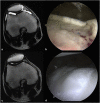

Case presentation: Two patients with osteochondral defect of the knee recovered from the disease enough to begin major exercise 1 year after hUCB-MSCs implantation. The IKDC, VAS, and Tegner score of the two patients showed an excellent improvement and concurrent arthroscopy was performed; cartilage regeneration of ICRS grade 1 similar to normal was observed. The modified two-dimensional MOCART scores increased in both cases over time.